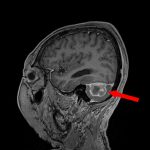

No.’25_60 手術前2